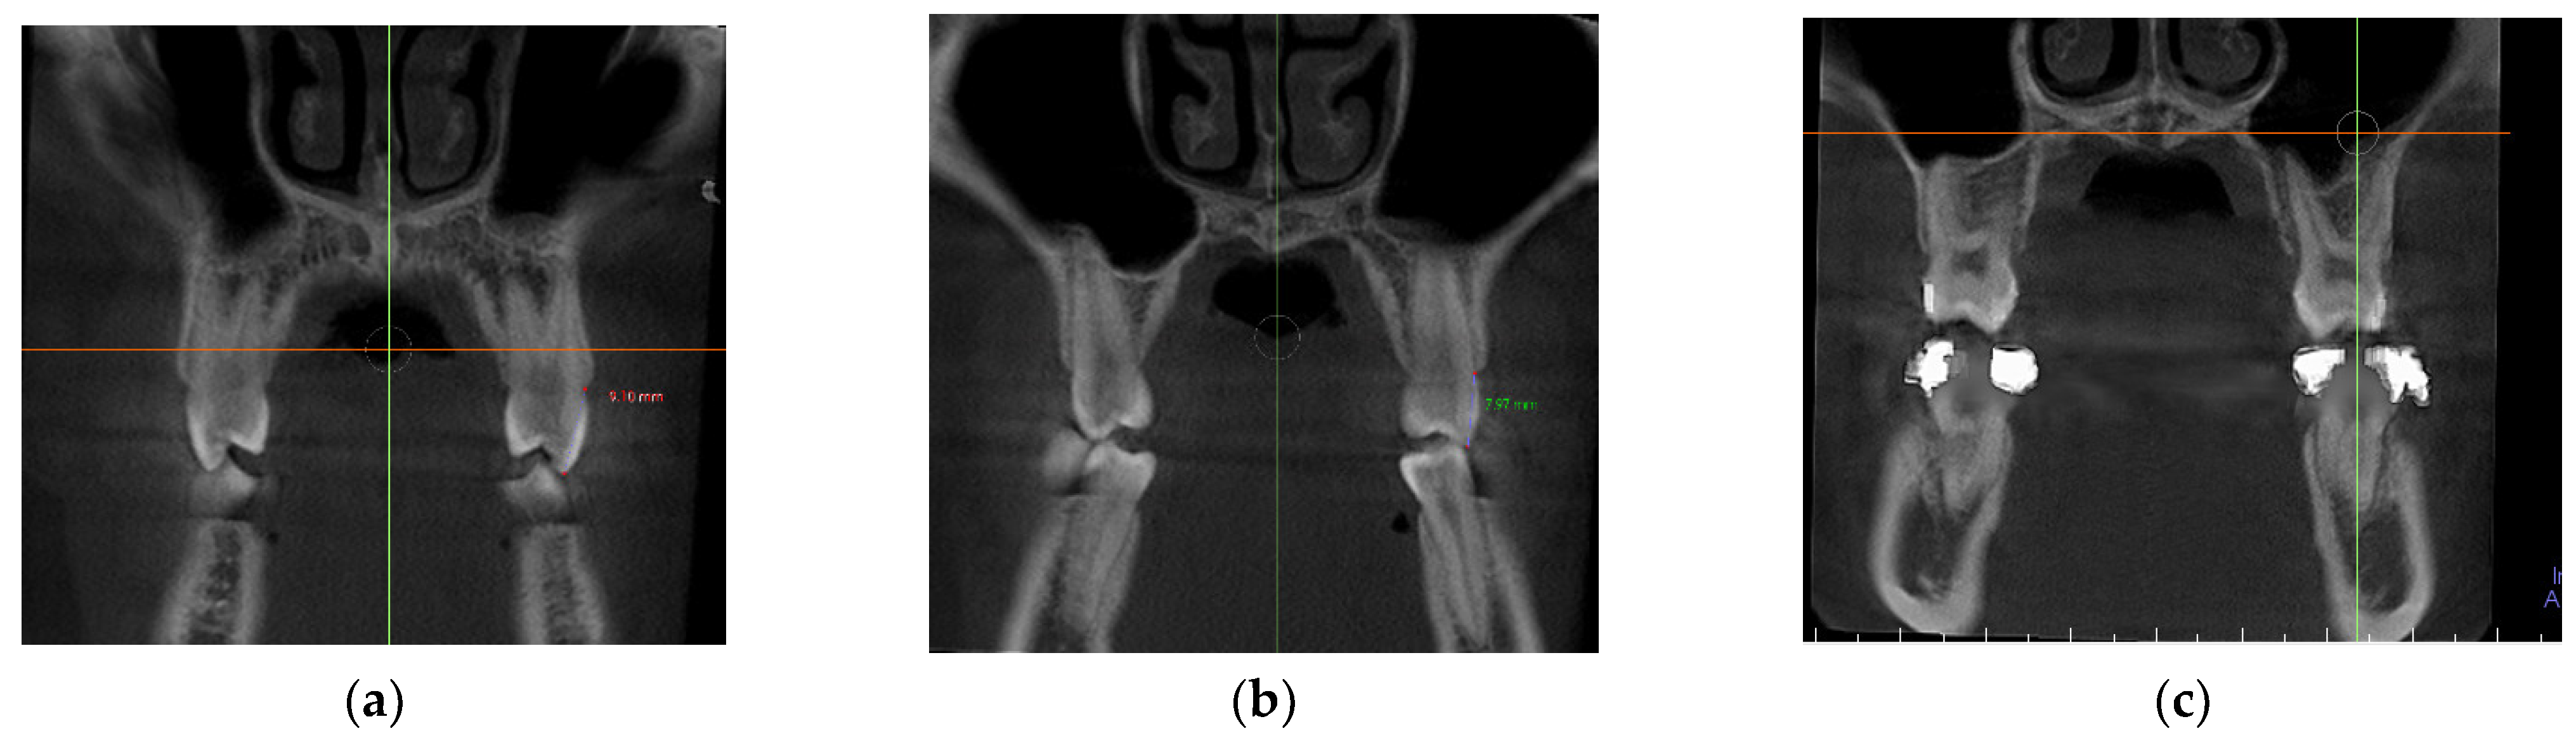

- In the coronal plane: For the first premolar and the first molar: cuts were made at the most anterior section where the crown and palatal root can be seen at their greatest length. For the second premolar: in the most anterior section showing maximum length of its root (Figure 2).